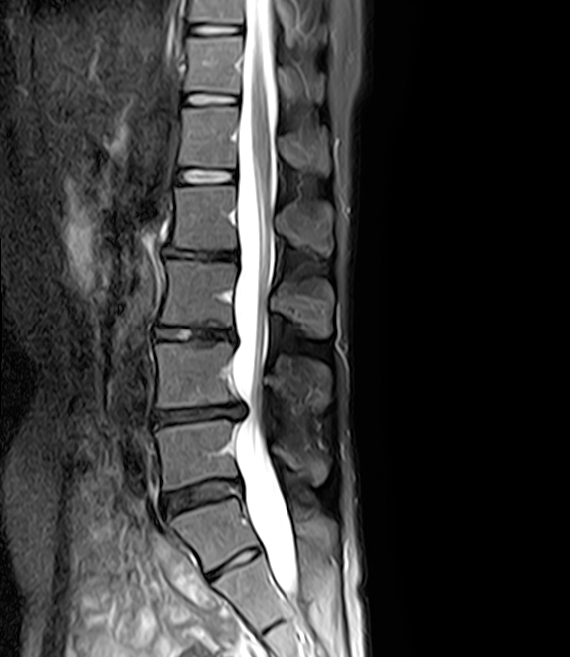

저는 허리가 너무 아파 고생한 50세를 바라보는 퇴행성디스크 환자입니다. 30대 초반부터 아팠으니.. 거의 20년을 수술 안 하고 잘 버티며 살아가는 중이네요. 아래 저의 MRI로 보면 모든 디스크가 까맣고 간격도 좁습니다^^;

통증이 심했던 2022년 초, 수술을 염두에 두고 유명한 대학병원 교수님 초진을 다녀왔었습니다. 찍어 간 MRI를 보시더니

"허리는 수술할 정도이나 환자 본인이 차츰 호전된다고 느끼니 성급하게 수술을 결정할 필요는 없다.

디스크 4개가 모두 안 좋아 다른 사람보다 노화되며 문제 일으킬 확률은 높지만 버텨라!"라고 말씀하셨습니다.

MRI상 디스크 상태보다 환자가 통증을 어느 정도 느끼는지가 수술을 결정할 때 중요시 여기는 부분인 것으로 보입니다.

24년 2월 현재까지 아직은 큰 통증이 없이 잘 지내고 있고 심한 통증은 없어 이후 MRI는 찍어보지 않았습니다.